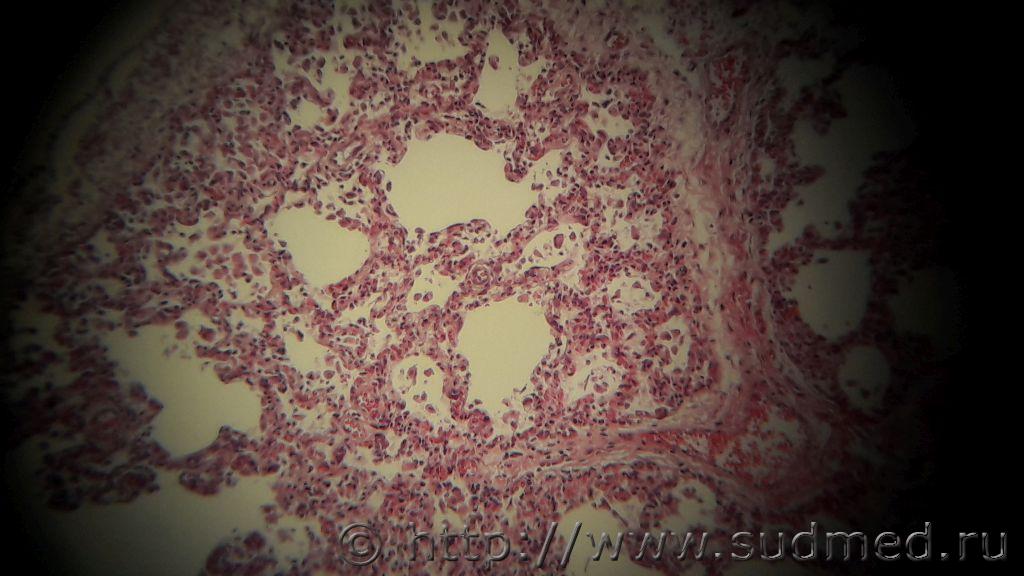

Добрый день, уважаемые коллеги. После одного случая мне у детей начала мерещиться почти всегда интерстициальная пневмония smile.gif Девочка 2 месяца, мама ВИЧ+. У самой девочки антитела есть, но достоверно ВИЧ не установлен, так как маленькая еще.

В препаратах легких встречаются вот такие очаги нейтрофильной инфильтрации

Но и на остальном протяжении легкие меня настораживают.

Не похоже на нейтрофилы.

В просвете некоторых альвеол видны пенистые массы + инфильтрация межальвеолярных перегородок лимфоидными клетками,гистиоцитами и,вероятно,единичными пневмоцистами (похоже на это),что позволяет предположить пневмоцистную пневмонию.

Больше соответствует к интерстициальной пневмонии, далее отек с геморрагическим компонентом и десквамация альвелоцитов.